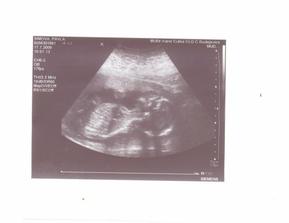

17.7. - VELKÝ utz v Českých Budějovicích, naštěstí nás pan doktor potěšil, naše miminko je v pořádku, bez známek vývojových vad a bylo krásně vidět, cucalo si prstíky a mávalo na nás 🙂), a jako bonus jsme se dozvěděli, že čekáme HOLČIČKU!!!!! Zatím máme vybrané jméno Terezka, ale myslím, že se to do porodu ještě změní 🙂)